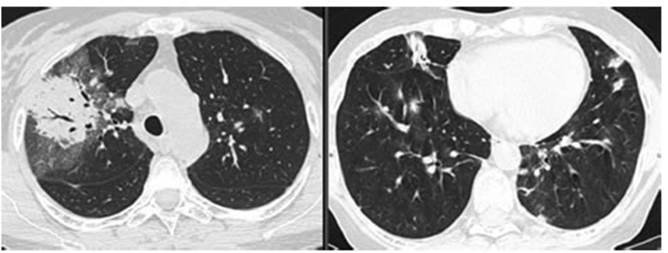

New CT requested 01/21/2022 (Figure

2): reduced bibasilar infiltrates with appearance of new inÂfiltrates in upper

lobes. Consolidation with air bronchogram

surrounded by “ground glass” opacities with interlobular septa thickening in

the anterior and posterior segment of the right upper lobe.